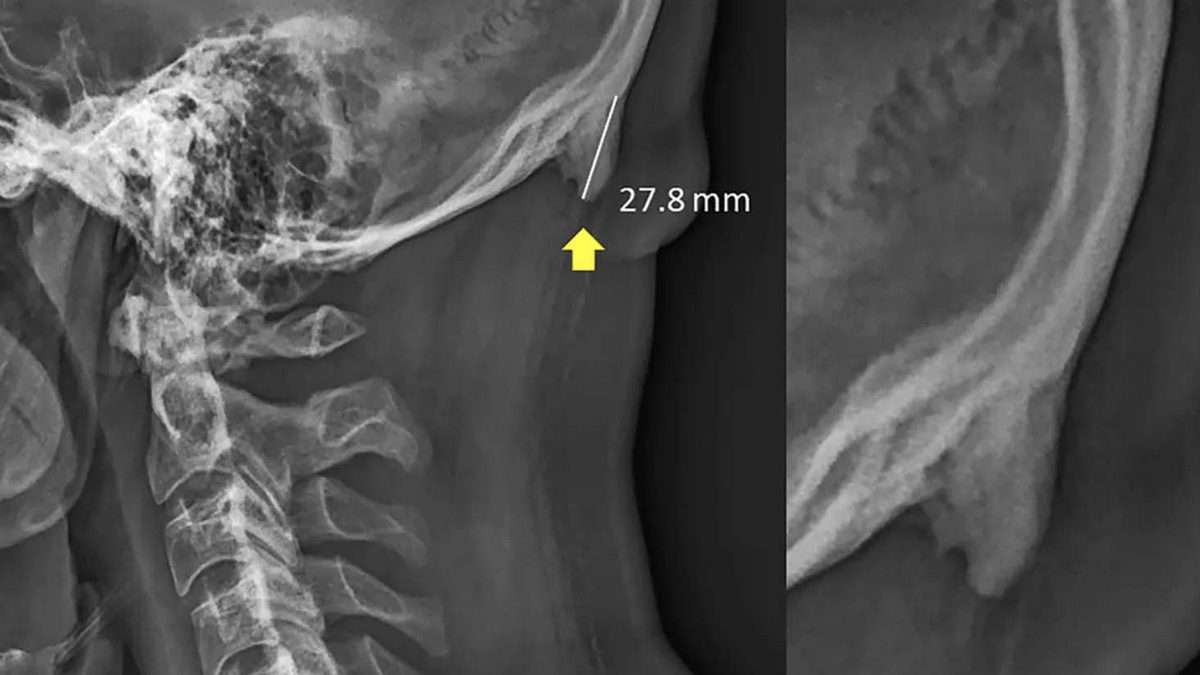

Photo Credit: Scientific Reports  தலையின் பின்புறத்தில் வளரும் எழும்பு

ஒருவர் நீண்ட நேரம் ஸ்மார்ட்போனை பயன்படுத்துகையில், அவர் நீண்டே நேரம் தலையை குனிந்தபடியே இருப்பார். இதன் அப்போதைய விளைவு கழுத்து வலி போன்று சிறிய பாதிப்பாக இருக்கும். ஆனால், இது அதிக நாட்களுக்கு தொடர்ந்தால், இதன் பாதிப்பு வேறு மாதிரி பெரிதாக இருக்கும். அந்த பெரிய பாதிப்பு எப்படியாக இருக்குமேன்றால், ஒருவரின் தலை மண்டையோட்டில் எழும்பு வளர்ச்சியாக இருக்கும். இந்த எழும்பு தலையின் பின்புறத்தில் கழுத்தில் மேலுள்ள மண்டையோட்டு பகுதியில் வளரும் எனவும் ஆராய்ச்சியாளர்கள் கூறியுள்ளனர். கழுத்தின் மேல் பகுதியில் வளரும் இந்த எழும்பு கொம்பு போலவே இருக்கும் எனவும் தெரிவித்துள்ளனர்.

ஆஸ்திரேலியாவின் குயின்ஸ்லாந்திலுள்ள சன்ஷைன் கோஸ்ட் பலகலைகழகத்தை சேர்ந்த இரண்டு ஆராய்ச்சியாளர்களே இந்த ஆய்வை மேற்கொண்டு, முடிவுகளை வெளியிட்டுள்ளனர். இந்த ஆய்வின் முதல் அறிக்கையை 2016 ஆண்டே வெளியிட்ட இவர்கள், 18 முதல் 30 வயது உள்ளவர்களில் 218 பேரை தங்களது ஆய்விற்குள் உட்படுத்திக்கொண்டனர். முதலில், அவர்களது தலைகள் எக்ஸ்-ரே எடுத்து வைக்கப்பட்டது. இந்த 218 பேரின் தலையையும் 3 வருடங்களுக்கு பிறகு தற்போது எக்ஸ்-ரே எடுத்து முன்பு இருந்த மண்டையோட்டு அமைப்புடன் ஒப்பிட்டு பார்க்கையில்,இதில் 41 சதவிகித்தினருக்கு, இந்த எழும்பு வளர்ச்சி கண்டறியப்பட்டுள்ளது.